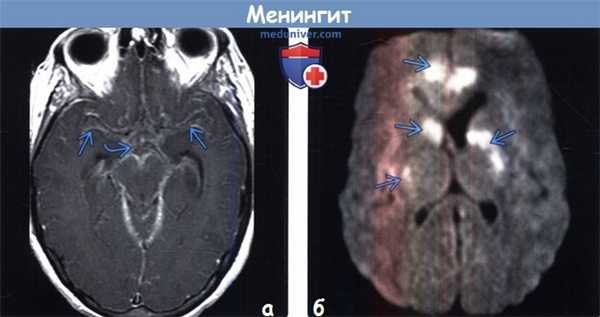

(а) КТ с контрастированием, аксиальный срез: у младенца с β-стрептококковым менингитом определяется контрастирование коры и лептоменинкс Обратите внимание на расширение передних рогов и III желудочка, что отражает нарушение циркуляции СМЖ.

(б) МРТ у того же пациента, выполненное по поводу эпилептического статуса, возникшего спустя 24 часа после КТ, постконтрастное Т1-ВИ, аксиальный срез: данный метод исследования позволяет более отчетливо визуализировать контрастирование коры и лептоменинкс по периферии лобных долей. При исследовании СМЖ с окраской по Граму были выявлены грамположительные диплококки. (а) МРТ, FLAIR, аксиальный срез: эта методика является чувствительным инструментом для выявления ранних сложных внемозговых скоплений жидкости. Определяется повышение интенсивности сигнала от коры правой лобной доли, а также в пределах субарахноидального пространства правых лобной и височной областей. Обратите внимание на раннее вовлечение субарахноидального пространства левой лобной области.

(б) МРТ, ДВИ, аксиальный срез: данная методика у этого же пациента с менингитом помогает отличить субдуральные выпоты от субдуральных эмпием. В зоне этих гиперинтенсивных субдуральных скоплений жидкости, расположенных в обеих лобных областях, определяются низкие значения ИКД.